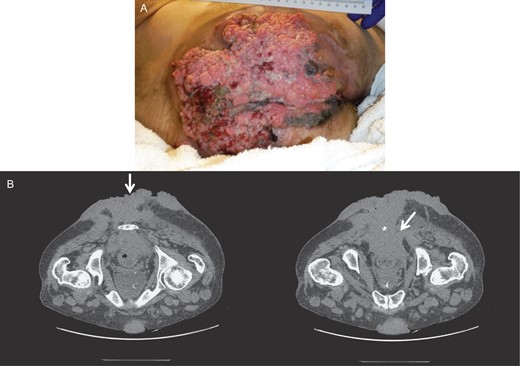

A 46-year-old male patient, of unknown sexual orientation, HIV-negative and history of alcohol abuse, was admitted to the hospital for diarrhea and purulent drainage of a foul-smelling, cauliflower-like lesion covering the bilateral buttocks. The patient had a history of multiple perianal condyloma acuminata that persistently recurred after a number of excisions and progressively enlarged over 20 years. On examination, a solid and fixed condylomatous lesion, measuring 27 × 20 cm2 (width × length) involved perineum, perianal area, and bilateral buttocks, from sacrum up to approximately the L4–L5 level. A fistula was also present along the right gluteal region, with the external opening measuring 2 cm in circumference and no signs of active infection. A computed tomography (CT) of the abdomen and pelvis showed a soft tissue density, measuring 14 × 11 × 17.7 cm3 (transverse × anteroposterior × craniocaudal), extending from the right posterolateral rectum, through the perirectal and presacral space, into the external buttocks (Fig. 1). Bilateral prominent inguinal lymph nodes were also noted. The colonoscopy showed involvement of the entire anal canal and rectum up to the distal sigmoid colon. The biopsy and histopathology showed condyloma acuminata with mild dysplasia and concluded a giant condyloma of Buschke and Löwenstein.

CT of the pelvis and perineum showing the BLT invading the rectum and anal canal.